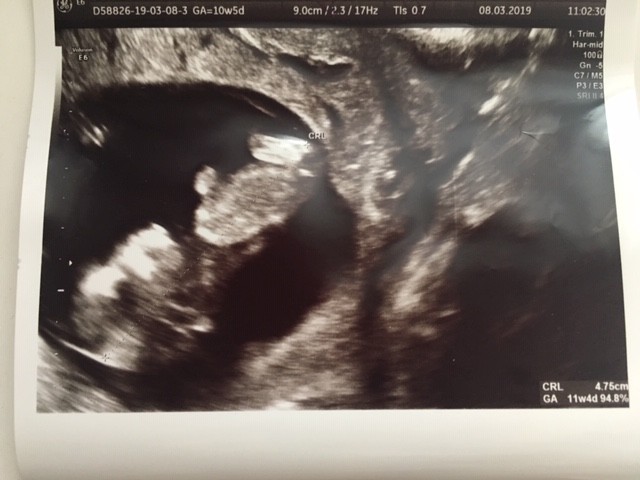

Nasze USG

07.03 :) crl 3,76